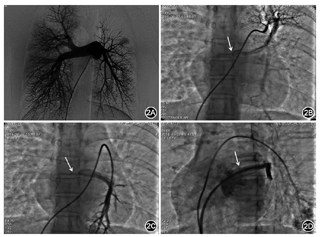

心导管检查:导管径路无异常,计算各部位血氧,体肺比1∶1;同时测定肺动脉压、左心房压及各部位肺毛细血管楔压。主肺动脉造影:左肺动脉普遍细小、稀疏,右肺动脉相对充血;再循环后可见右下肺静脉呈瘤样曲张,与右上肺静脉共同回流至左心房。为进一步明确左侧肺静脉解剖形态,在左上和左下肺小动脉分别造影,静脉相显影证实左上、下肺静脉共汇同一静脉干回流至左心房,伴入口局部重度狭窄(图2)。介入治疗:穿刺房间隔将200 cm 0.018 inch(1 inch=2.54 cm)(Boston ScientificV-18 Control Wire)导丝通过左肺静脉狭窄段血管,以4 mm×30 mm小球囊(Boston Scientific Sterling)在狭窄处预扩张,然后植入Express LD10×37 mm球囊支架(Boston Scientific)。复查造影示狭窄解除,支架贴壁良好,血流通畅,且不影响肺静脉分支(图2)。左肺静脉狭窄远端压力由28 mmHg下降至11 mmHg,肺静脉与左心房的压差消失,肺动脉平均压则由35 mmHg降至22 mmHg(表1)。